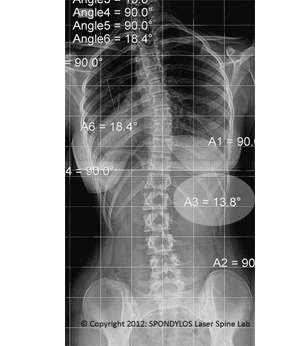

Results in Adolescent Scoliosis 5

Teenager with a big right thoracic scoliosis 61,7⁰. She applied a SPONDYLOS Rigo-Cheneau brace, where since the trial fitting the trunk ballanced with the center of gravity (red line) and in x-ray in brace the scoliosis was corrected in 29⁰. The patient after 30 months is still aligned and maintains the angle of correction.